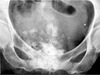

frontal sinus osteoma